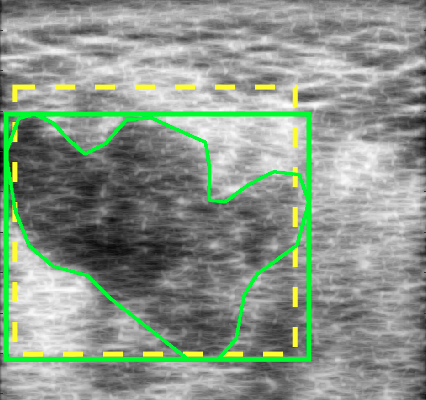

In [15], only “global” barcodes were used, meaning that one barcode was extracted for the entire image. But it was recognized that using “local” barcodes may be of more significance when dealing with specific regions of interest (ROIs) (see Fig. 2). In this research, the two were combined and every image was tagged with two barcodes. The “global” barcode captures the general appearance of the image, and the “local” (or ROI-based) barcode captures the texture and intensity variations of the tumour.

Assuming that there is a set of training images along with their ground-truth segments, we propose to use barcodes in order to estimate the location of a bounding box around the tumour (contoured by the expert as a ground-truth) with starting coordinates and ending coordinates (Fig. 4). Two barcodes were assigned to each bounding box: a global barcode for the entire image, and a local barcode for the bounding box (Fig. 5). The rough localization of a bounding box for the tumour can be formulated as a search problem: given a database consisting of training images with their corresponding bounding boxes , and global and ROI Radon barcodes , the bounding box was formulated for a query image by first finding the top similar images in the database via Hamming distance between corresponding barcodes: